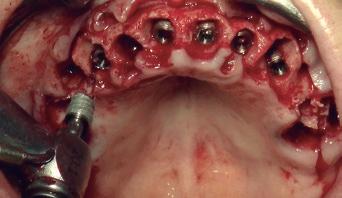

FIG. 5. Colocación de implantes. FIG. 6. Electrosoldadura intraoral. FIG. 7. Prótesis provisional.

de las piezas dentales restantes en boca de ambas arcadas y se procede a la preparación del lecho óseo con un legrado minucioso previo a la colocación de los implantes. Seguidamente con un bisturí N.º15, se lleva a cabo una incisión lineal a espesor total y el posterior despegamiento (fig. 4). Con una velocidad de 1.000 rpm, se efectúa la secuencia de fresado acompañada de una irrigación ininterrumpida con suero fisiológico. A continuación, se introducen los implantes de la marca Radhex® (fig. 5) y se cierra la herida con puntos simple de sutura reabsorbible de ácido poliglicólico de 4/0. Posteriormente, se colocan los pilares transgingivales, modelo PMU de la marca Radhex®, junto a los pilares de carga inmediata modelo PRO de la marca Radhex®, sobre los cuales estará soportada la prótesis provisional superior. Mediante la técnica de electrosoldadura se ferulizan los pilares con cuatro barras de titanio, dos de un grosor de 1,5 mm y dos de un grosor de 1 mm (fig. 6). Una vez finalizada la ferulización en ambas arcadas, se confeccionan las prótesis provisionales superior e inferior para el restablecimiento de las funciones orales y estética de forma inmediata desde el día de la cirugía (fig. 7). Tras el periodo de osteointegración, se realiza la toma de registros y medidas para su posterior envío al laboratorio con el fin de, mediante tecnología CAD-CAM, confeccionar la estructura metálica de la prótesis definitiva (fig. 8). Una vez finalizadas las pruebas, se le coloca y ajusta la prótesis definitiva al paciente. Se le dan instrucciones de higiene oral e indicaciones de los controles periódicos a los que debe acudir para verificar que tanto las prótesis como los implantes se encuentran correctamente y en óptimo estado (figs. 9 y 10).